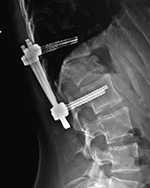

| Lumbar spine bony disk strut, pedicle screws, and pedicle rods (AP view) |

Lumbar spine bony disk strut, pedicle screws, and pedicle rods (lateral view) |

| There is an anterior allograft bone strut used to treat metastatic neuroblastoma in the L4 vertebral body. The bone strut crosses both the pathologic vertebral body as well as its adjacent disk. The anterior position of the bone strut is typical for these struts. From Hunter, 2004 |